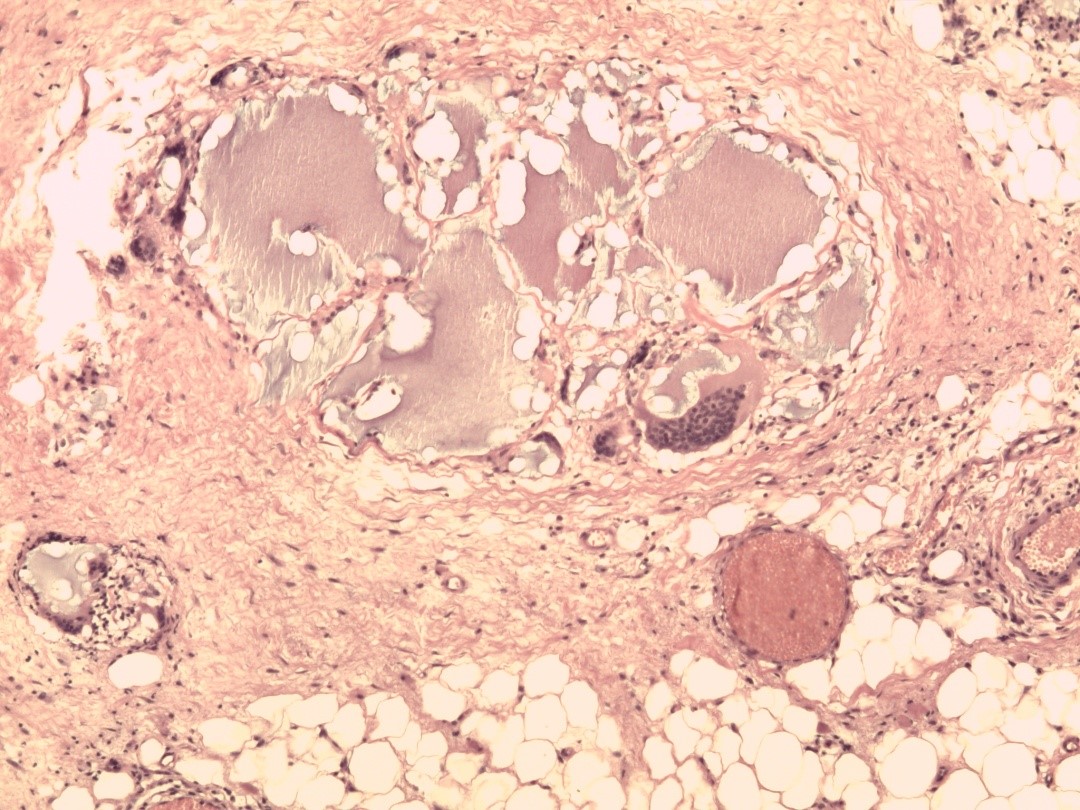

Ни в одном из наблюдений после вмешательства с применением ВПП в различных режимах не выявлено морфологических признаков острого воспаления. В поле зрения были отмечены лишь единичные микроскопические локусы ПААГ, основная масса которого, вероятно, подверглась высокоэнергетической вапоризации (рис. 6). Их размеры были сопоставимы с размерами самых крупных адипоцитов.

Рис. 6. Гистограмма биоптата молочной железы после плазменно-физической обработки на 5-е сутки. Окраска гематоксилином и эозином (×40).

К 5-м суткам явления хронического продуктивного воспаления с лимфоидной и плазмоцитарной инфильтрацией хотя и наблюдались, но были менее выражены, чем в исходных гистограммах. Количество гигантских многоядерных клеток уменьшилось на несколько порядков. Сохранялись микроциркуляторные расстройства, однако признаки дезорганизации соединительной ткани были незначительными и носили уже очаговый характер (рис. 7). На фоне регулярной плазмадинамической санации (NO-терапия) замечено раннее появление очагов фибробластической пролиферации и краевой эпителизации. Постепенно формировалась полноценная грануляционная ткань и кровеносные сосуды, хотя местами еще отмечались признаки умеренных микроциркуляторных расстройств.

Рис. 7. Гистограмма биоптата молочной железы на фоне плазмадинамической санации (5-е сутки). Окраска гематоксилином и эозином.